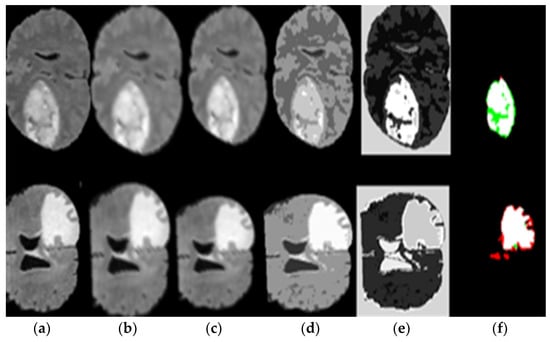

- The pre-processing stage is through an enhancement filter, to improve the image; we introduce a new fusion method. In this step, the input MR brain images were resized by 256 × 256 × 1. Then, we choose a high pass filter to improve the edges of the input MR brain image. The input and output of the MR brain image are fused serially. Finally, a combined, fused MR brain image is smoothed using a 3 × 3 median filter that gives the excellent effect of segmentation results compared with previous models.

- We applied a seed-growing algorithm based on the optimal threshold for good segmentation for a brain tumor.

4.3. Segmentation Using a Seeded Region Growing

4.4. Softmax Classifier